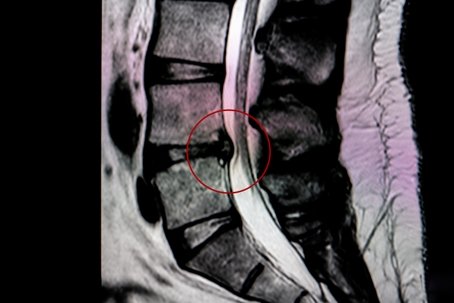

Xray of a herniated disc

3. MRI: This is the preferred method for visualizing herniated disks, as it provides clear images of soft tissues without using radiation.